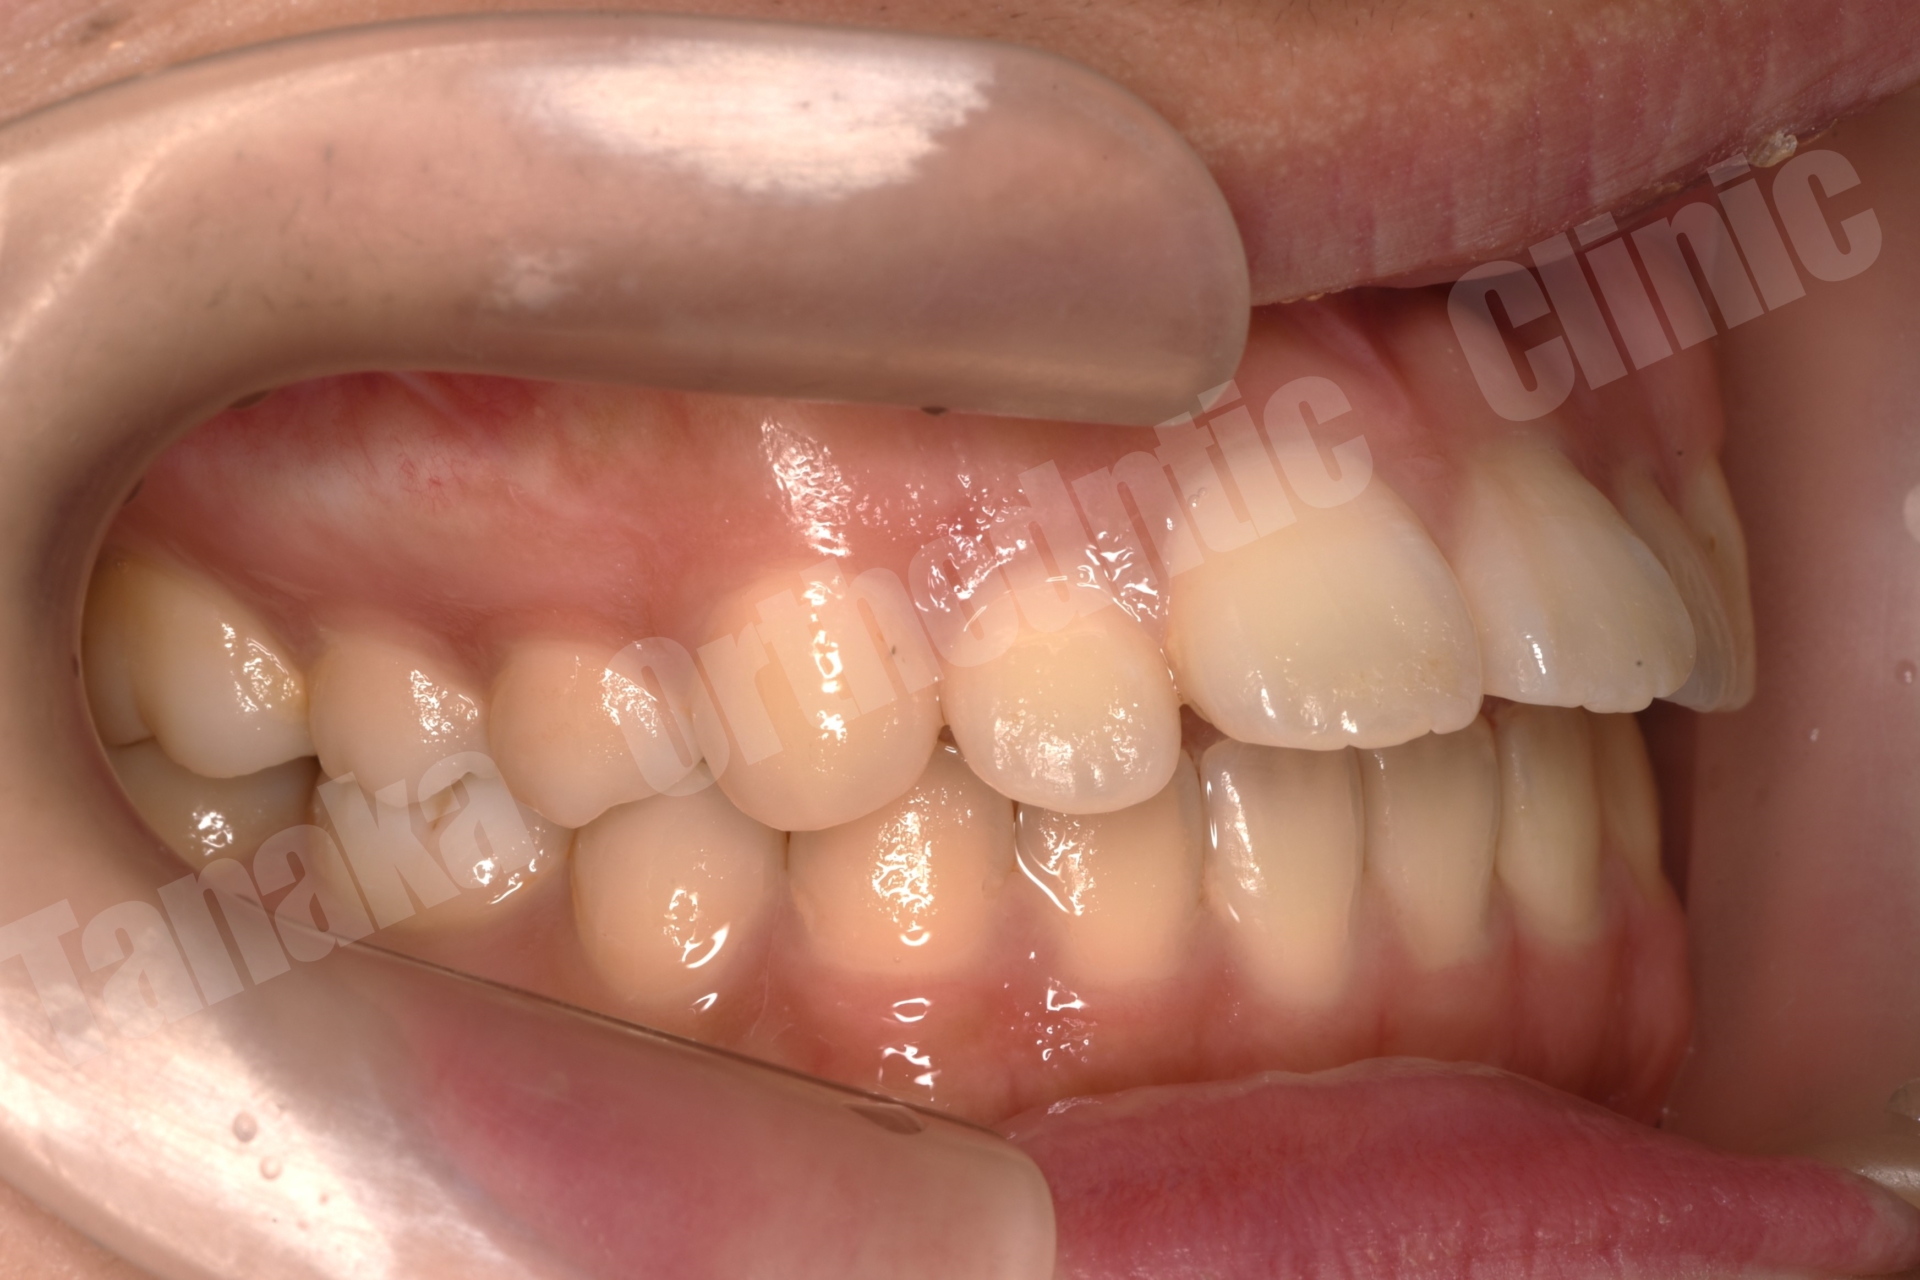

初診時の診査では、上顎前歯が唇側に傾斜しており、前歯の水平被蓋(オーバージェット)が大きい状態でした。そのため口元の突出感が認められ、前歯部は十分に噛んでいない状態でした。また下顎正中は左側へ偏位しており、右下E(乳臼歯)の残存と5番の先天欠如、さらに下顎両側7番の位置異常も確認されました。さらに患者様は10代半ばの頃に一度、非抜歯でマルチブラケット矯正を受けており、その影響もあって上顎中切歯には歯根吸収が生じ、歯根がやや短くなっている所見も認められました。

そこで治療では上下歯列に唇側マルチブラケット装置を装着し、歯列全体の排列を行いました。上顎前突を改善するため上顎両側4番を抜歯し、前歯を後退させて口元のバランスを整える計画としました。さらに下顎正中の改善のため右下Eを抜歯し、約11mmある乳臼歯部のスペース閉鎖を行う計画としました。このスペース閉鎖には矯正用アンカースクリューを使用し、右側6番・7番を近心移動させる必要があります。また治療途中で萌出してくる右下7番の位置を適切にコントロールすることも重要なポイントとなります。